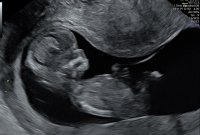

Fikk veldig fine bilder i dag! Fortsatt sprellete, men ikke så mye som sist hehe. Gyn mente ho også er godt over 90% sikker på kjønn. Fikk det i en konvolutt for å åpne med mannen senere:D

13+0 etter mens, målt til 13+6. Blir nok en februarbebis på oss!